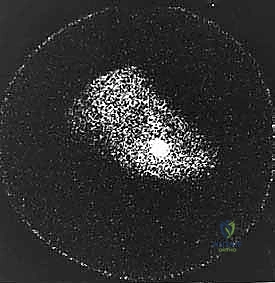

Figure 5A: Triple-phase bone scan showing increased uptake in the tibial sesamoid region on an AP view of bilateral feet.

Figure 5B: Collimated view of the bone scan, clearly delineating the increased uptake in the tibial sesamoid.

Figure 5A: Another triple-phase bone scan image.

Figure 5B: Another collimated view from a triple-phase bone scan.